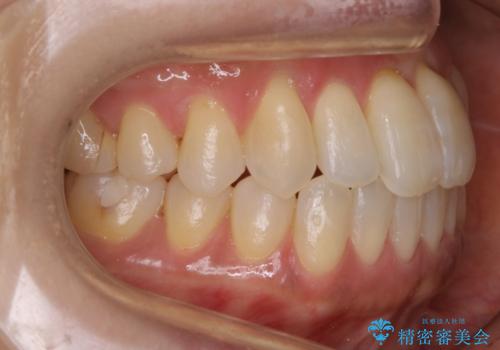

- 矯正装置

- マウスピース(インビザライン)

- 治療期間

- 1年

- 治療回数

- 10-30回

- 税込 ¥770,000- (インビザライン コンプリヘンシブパッケージ)費用は治療当時の料金となります